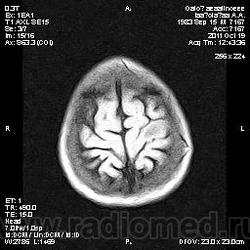

Колеги, спасибо за высказывания. В данном случае про наркоманский анамнез указано не спроста... Есть мнение, что в этом лежит точка отсчета.... По поводу абсцесса и гематомы - не согласен; по поводу первого - нет соответствющей клиники, по поводу второго - не характерна локализация и сигнальные характеристики. Не буду томить общественность касательно собственного мнения. Есть две гипотезы, о которых думается в данном случае: прогрессирующая лейкоэнцефалопатия и новообразование... Но без контраста их не разрешить...

пожалуй "первое", но в отношении "второго"смущает "круглит" на вершине "воспалительной демиелинизации", который она (демиелинизация) так странно обходит...

Имеются  в виду последние 2 картинки?Мне тоже так показалось.А почему контрастирования не будет?Чем контрастируете?